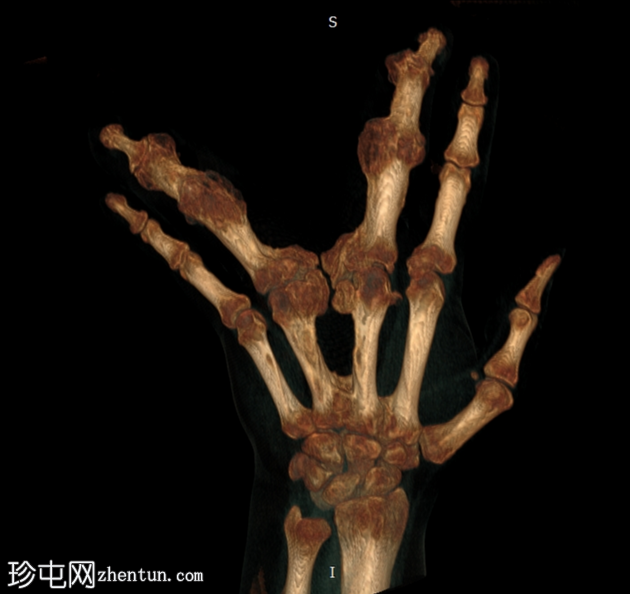

无名指和中指明显增大。患者掌骨和指骨骨质增生肥大,并伴有周围皮下脂肪过度增生。

CT 扫描显示骨质过度生长和肥大、皮下脂肪过度生长以及神经纤维脂肪瘤性错构瘤。

脂肪瘤性巨营养不良症 (MDL) 是一种罕见的先天性疾病。该病与 PIK3CA 基因突变有关。病理学上,脂肪瘤性巨营养不良症表现为所有间叶成分增多,脂肪组织过多,以及其他组织,如骨膜、骨髓、神经鞘、肌肉和皮下组织(局部巨人症)。

该病通常与神经纤维脂肪瘤性错构瘤有关。受影响的肢体通常遵循上肢正中神经的分布,就像本例一样。